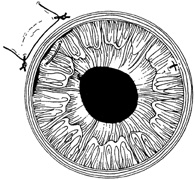

Tissue adhesive should be applied to a dry, deepithelialized bed. A capillary microapplicator or fine-gauge disposable needle is used to apply a very thin film of adhesive over the site (Fig. 3). Alternatively, adhesive may be applied using a sterile 2- to 4-mm polyethylene or silicone disc affixed to the end of an applicator stick with sterile ophthalmic ointment. The disc may be left in place or removed with care. Three to five minutes are required for polymerization of the adhesive. A bandage soft contact lens is applied for comfort and to prevent the glue from dislodging. While the contact lens is in place, a prophylactic antibiotic drop is administered. Over time, the tissue adhesive dislodges spontaneously as the wound surface reepithelializes. Alternatively, it may be gently removed with forceps after adequate stromal healing has occurred.